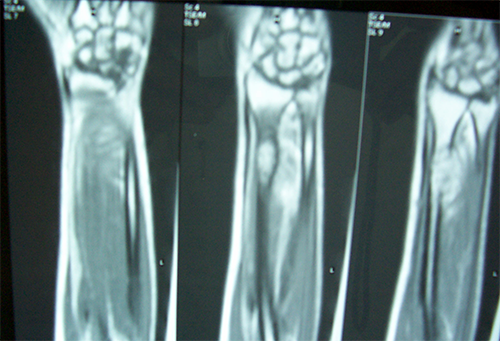

Case:2 GCT-L/E Radius

Pre-Op

Post-Op AP

Post-op Lateral

Imm Post-op

MRI-AP View

MRI